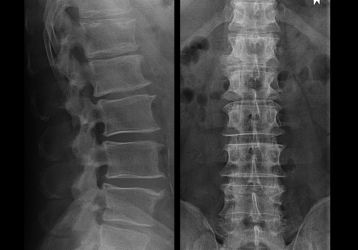

Заболевания и боли в разных отделах позвоночника: причины, симптомы, лечение

Упражнения при остеохондрозе поясничного отдела позвоночника: как правильно выполнять, видеоинструкции

Как правильно выполнять упражнения при остеохондрозе поясничного отдела позвоночника, в каких случаях этого делать нельзя. Техника выполнения упражнений.